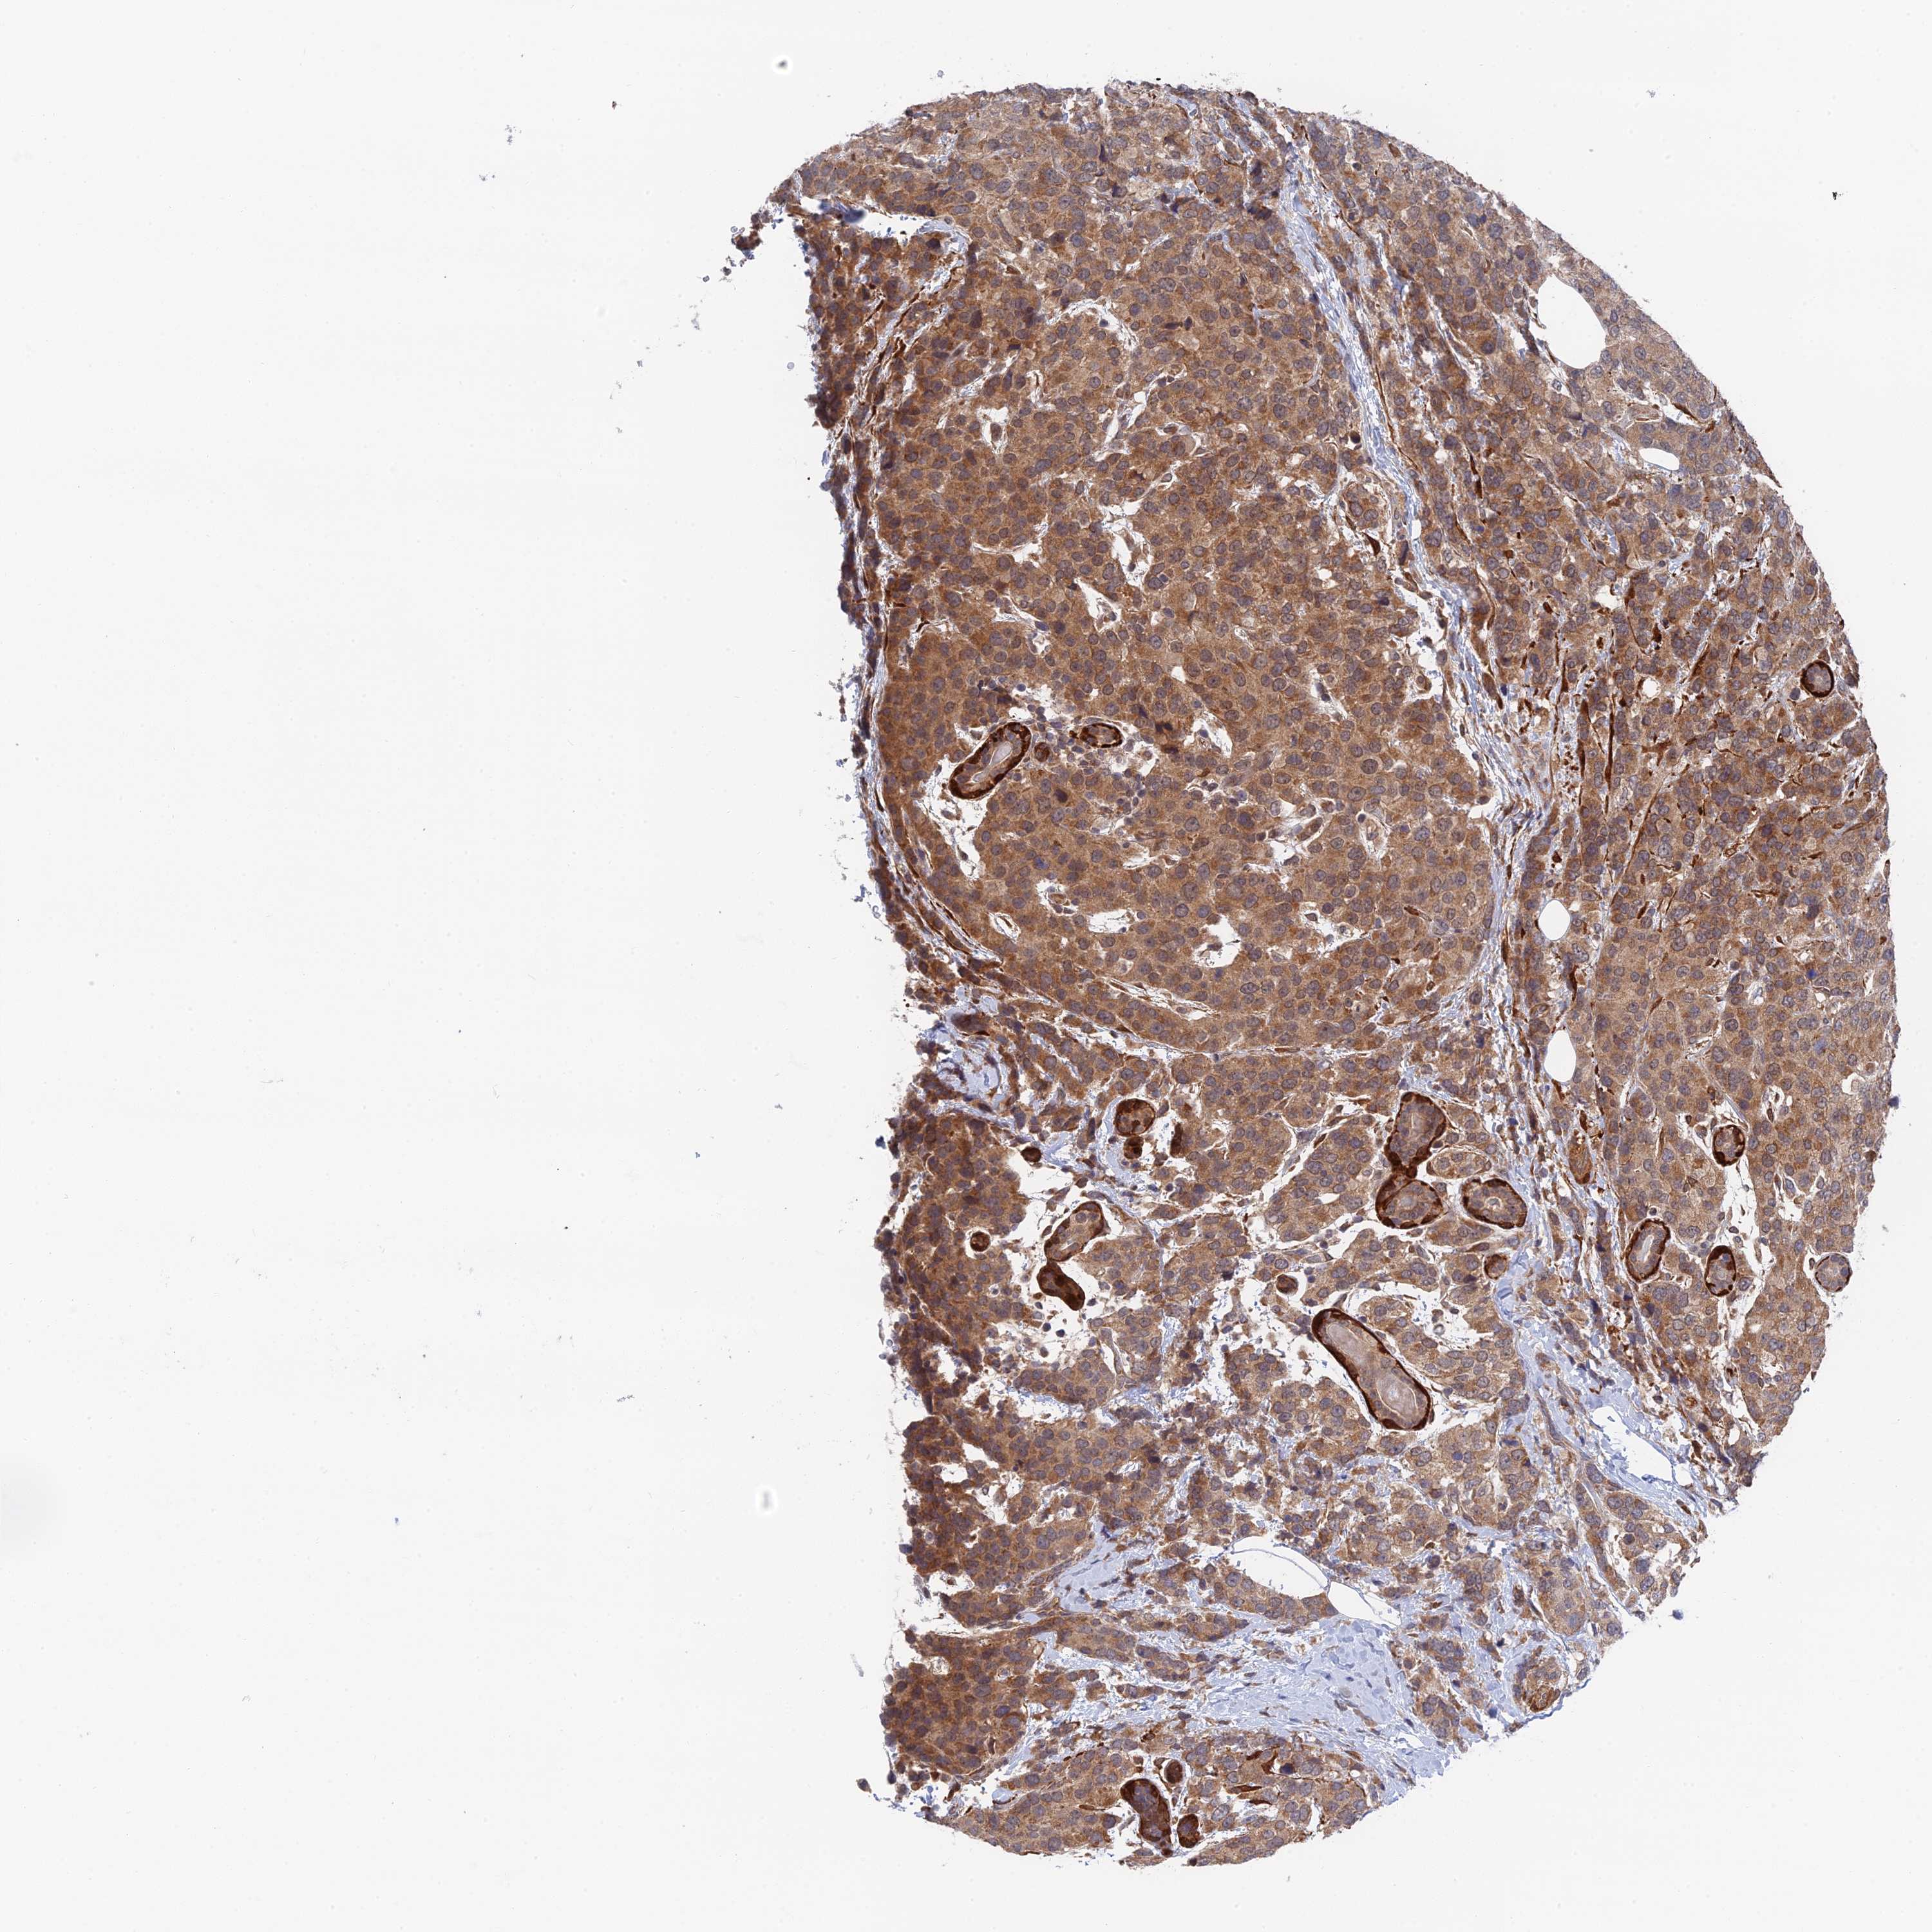

CANCER BREAST CANCER Show tissue menu

BRCA TCGA BRCA VALIDATION PROTEIN EXPRESSION

Breast cancer

Human cancer

Breast invasive carcinoma